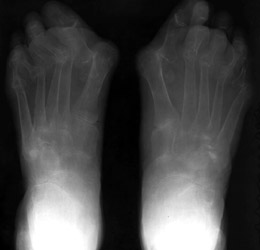

Rheumatoid

arthritis (RA) is a disease of the synovium. The hallmarks of rheumatoid

arthritis are symmetrical joint involvement, marginal erosions, uniform joint

space narrowing, juxta-articular osteoporosis, and soft tissue swelling. There

is a lack of hypertrophic changes. However, secondary osteoarthritis may lead

to productive changes.

1. Distribution:

There is involvement of the appendicular skeleton with sparing of the

axial skeleton except cervical spine. Hands, feet, knees, hips, cervical spine,

shoulders, and elbows are involved in decreasing order of frequency. Rheumatoid

arthritis of the feet involves mainly MTPs, first IP, and tarsal joints.

2. Erosion pattern:

Early erosive changes are seen involving the "bare areas" of

metatarsal heads. In late stages of RA, subluxations may occur at the MTP

joints with the proximal phalanges subluxating in fibular direction and metatarsal

heads subluxating in plantar direction. Tarsal bones are involved as a unit

with uniform joint space loss. Bony ankylosis of tarsal bones may occur. In

addition, erosions of the calcaneus may occur at the attachment of the plantar

aponeurosis and/or attachment of Achilles tendon.